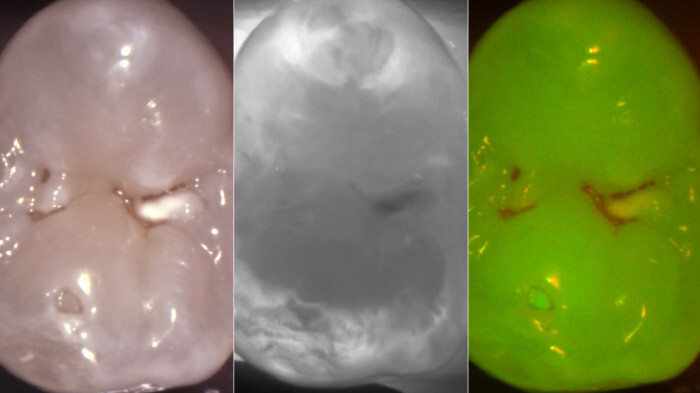

多くの細菌は、体内にプロトポルフィリンIX(PPIX)という物質を蓄積しています。近年、波長405nmの光を照射することで、細菌の持つプロトポルフィリンIX(PPIX)が赤色の蛍光を発することが明らかとなりました(Kühnisch J et al. 2004)。

そして、う蝕原因菌もPPIXを持ち、405nm光の照射で赤く光ることが報告されています(Michi Y et al. 2017)。

この技術を応用すれば、う蝕原因菌が多く集まりやすい=う蝕になりやすい部分を知ることができ、患者さんに特にしっかり歯ブラシを当てるようにアドバイスを行ったり、定期健診時に注意深く観察することで、う蝕を予防することができます。

また、う蝕を治療時する際にも、赤く光る部分を確実に取り除くことで、う蝕原因菌の高精度な除去が期待できます。さらに、赤く光る部分のみを選択的に取り除くことで、う蝕原因菌に感染していない健康な歯の不必要な削除も避けることができます。

このように波長405nmの光を照射することでう蝕原因菌を赤く光らせる方法として、蛍光モードを搭載したマイクロスコープ(EXTARO 300FV; Carl Zeiss)や口腔内カメラ(DIAGNOcam; KaVo Planmeca)などが挙げられます。

3種類の画像はフルHD解像度で撮影し、どんな症状であるかを鮮明な画像から得ることが可能です